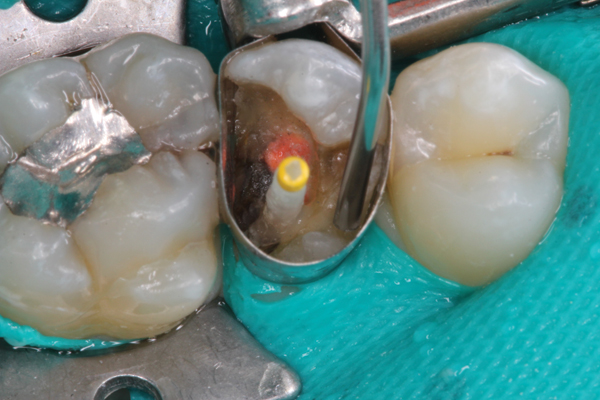

Another possible clinical application of bulk-fill composites is for use as a core build-up material. A clinical case demonstrating this technique is presented in Figure 7 through Figure 9. Build-ups are often placed into large, deep preparations with pins or a post. Therefore, important characteristics to consider for these materials are their shrinkage stress, depth of cure, flow, and toughness/strength. Flowable bulk-fill composites are desirable materials to use for build-ups because they have appropriate flow to adapt to a post or pin, low shrinkage stress, and high depth of cure, allowing them to be placed in bulk with the strength and toughness of a resin composite.

(7.) Post placed in tooth No. 13.

Figure 7

(8.) First layer of core build-up in tooth No. 13 placed.

Figure 8